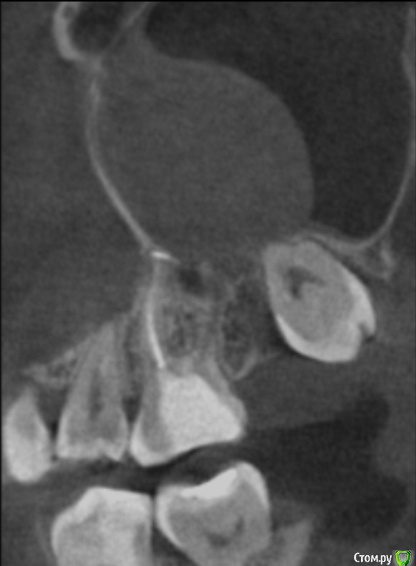

tineola Опубликовано 11 марта, 2017 Поделиться Опубликовано 11 марта, 2017 (изменено) Уважаемые врачи, здравствуйте! Мне 31 год, пол женский. Хронология:1. Ноябрь 2015 г. - септопластика и удаление кисты в левой гайморовой пазухе.2. Июль 2016 г. - со стороны этой же пазухи пролечены каналы 6-ки, через неск. дней удалена соседняя 7-ка (опустился почти до десны, беспокоил, ортодонты сошлись во мнении, что надо удалять).Через неделю появились незначительные боли в 6-ке, возникающие безотносительно нагрузки на зуб и еду. На прицельном рентгене корни 6-ки и лунка от 7го зуба были в порядке. Стоматолог уверял, что боль вызвана заживлением лунки от удаленного зуба и много других версий. Поэтому я ждала улучшений и терпела все это время.3. В последние недели боль усилилась: возникает при поворотах, наклонах головы, появились головные боли, головокружения, заложенность в носу. Сделала КТ конкретной области беспокоящего зуба, на которой видно новообразование в левой гайморовой пазухе, как бы лежащее на корнях беспокоящей 6-ки. Стоматологи предполагают, что киста от зуба мудрости (т.е. одонтогенная), возможно, рецидив первой. К посту прикрепила:1. ОПТГ (сделана до лечения 6-ки и удаления 7-ки, но после септопластики и удаления кисты).2. Фото из свежей КТ зубов с разных ракурсов, где хорошо видно новую кисту; ссылка на Яндекс-диск с архивом этого КТ (около 350 Мб) - https://yadi.sk/d/9omJkw6x3Efc6u3. Фото одной из проекций из старой КТ ОНП до септопластики, так выглядела старая киста. 4. К сожалению, результатов гистологии первой кисты у меня нет. В центре, где меня оперировали заключение не отдали, только сказали на словах, что все в результатах нормально. Попробую на руки получить...Очень интересует ваше мнение об увиденном на снимках.Правильно я понимаю: киста от зуба мудрости? удалять надо в ЧЛХ зуб с кистой вместе? Не пострадали ли от долгого ожидания решения проблемы корни 6-го зуба? Заранее большое спасибо за помощь! Изменено 11 марта, 2017 пользователем tineola Ссылка на комментарий

tineola Опубликовано 15 марта, 2017 Автор Поделиться Опубликовано 15 марта, 2017 (изменено) Сделала несколько скриншотов, прикрепляю к сообщению. Надеюсь, это то, что нужно.Может у кого-то из врачей будет время и возможность посмотреть КТ (ссылка в первом сообщении поста). Получила результаты гистологии первой кисты пазухи, которая год назад была удалена:Микроописание: Присланный материал представлен фрагментом полипозно-отечной слизистой оболочки, с концевым отделами слизисто-серозных желез. Эпителий слущен, гиалиоз базальных мембран, строма резко отечна, с диффузной лимфоцитарно-лейкоцитарной инфильтрацией. Патзаключение: хронический воспалительный процесс. Изменено 15 марта, 2017 пользователем tineola Ссылка на комментарий

tineola Опубликовано 15 марта, 2017 Автор Поделиться Опубликовано 15 марта, 2017 Еще скриншоты. Другая проекция из КТ. Ссылка на комментарий